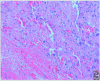

Masson's Tumor of the Finger

Keywords: Masson's tumor; finger; hand mass; intravascular papillary endothelial hyperplasia; organizing thrombus.